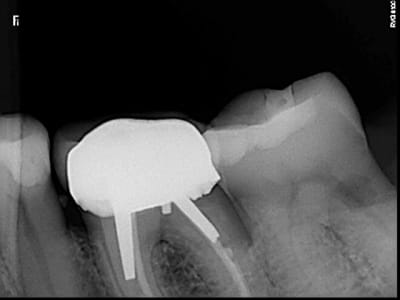

Bonjour, la patiente présente les signes d'une pulpite débutante sur 37 et à la radio j'ai trouvé çà : une lacune (érosion interne?) de forme atypique...j'ai pris plusieurs clichés avec angulations différentes.

Quelqu'un sait il ce que c'est ? Le diagnostic ? J'envisage le TC, des précautions particulières ?

Si ce n'est pas une lésion externe (noter la perte osseuse au niveau de la racine distale), ce serait plus une résorption interne qu'une érosion interne, non?

Je confirme, aucune lésion externe vestibulaire, distale ou linguale. Résorption interne ou lacune à angles nets, quelles sont les causes ? Traitement spécifique ou endo traditionnelle ? (je suis la patiente en paro depuis plusieurs années).

POur confirmer ton diagnostic tu dois avoir 2 rétro alvéolaires dont une décentrée de 30°. Tu peux également faire un conbeam bien que pas indispensable.

Le traitement est simple il faut faire le traitement canalaire car l'évolution de résorption interne est plus rapide qu'une externe. obturation gutta chaude.

nicklebenou : oui c pour etre sure que j'ai pris 2 autres clichés un distalé et un mésialé.

Entre la première et la deuxième radio, tu as clairement un décalage de la lésion.

De plus les contours du canal distal sont très nets sur toutes les radios

On devine une résorption osseuse sur cette racine distale

Donc pour moi tout indique que c'est externe

Même si je n'en suis pas certain à 100%. On voit bien le canal distal défini en effet derrière la lésion de résorption. Après je pense que les clichés sont décalés ne le sont pas assez pour se faire une meilleure idée mais il semble que la lésion soit décalée entre les clichés 1 et 2 par rapport au canal donc externe aussi.